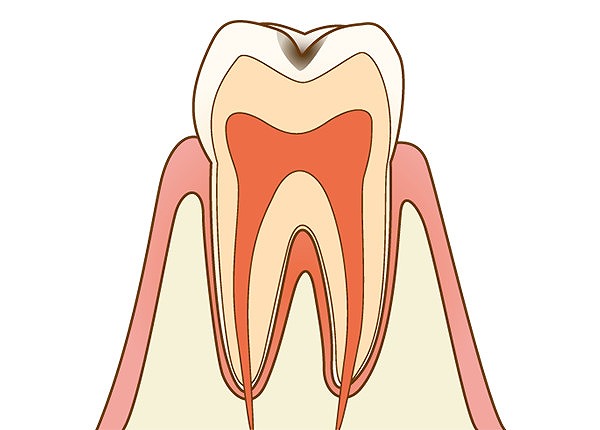

C2:象牙質のむし歯

エナメル質の内側になる象牙質がむし歯菌に侵されています。冷たいものがしみる、噛んだ時などに痛みを生じるといった自覚症状が現れはじめます。

エナメル質の内側になる象牙質がむし歯菌に侵されています。冷たいものがしみる、噛んだ時などに痛みを生じるといった自覚症状が現れはじめます。

むし歯菌に侵された部分を削り、詰め物で補って治療します。